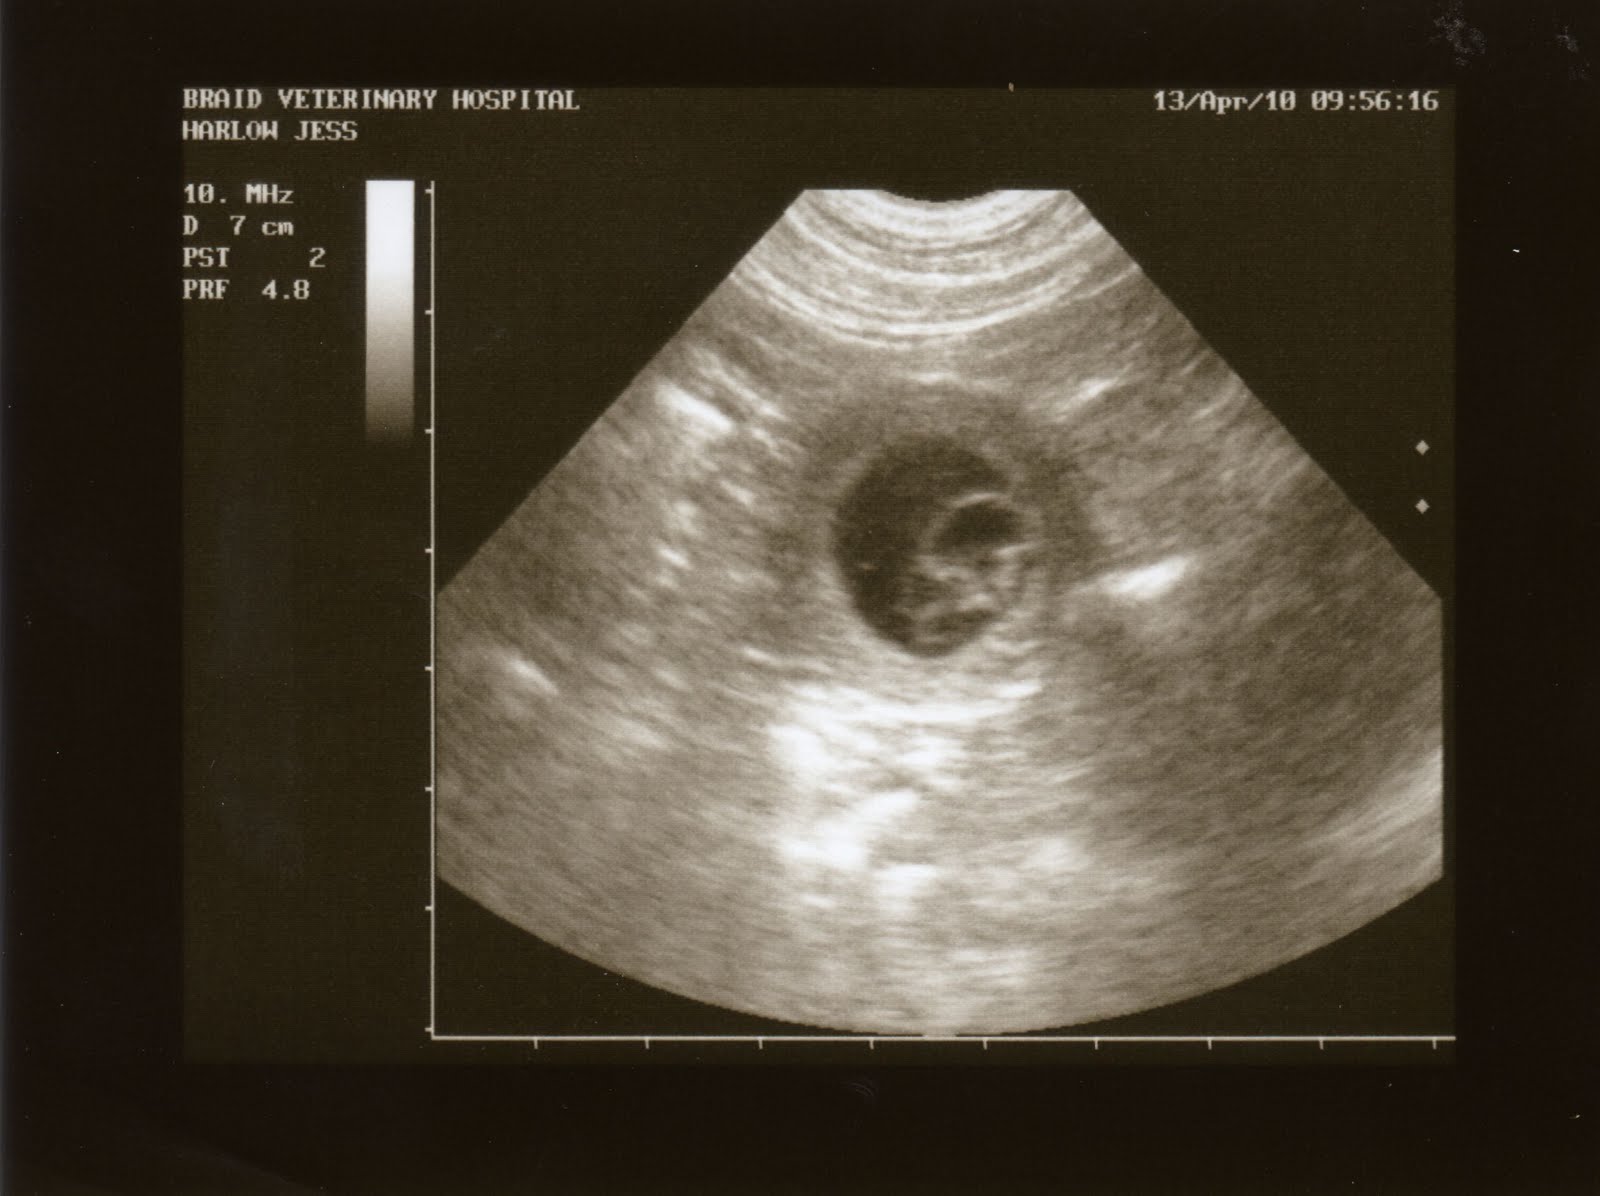

Фото плода на 4 акушерской неделе беременностиБудущий малыш на фото с УЗИ на этом сроке выглядит как маленькое зернышко, его размер сейчас всего 1 мм.

Во время развития плода ультразвук является одним из ключевых методов обследования.

Точного графика проведения УЗИ не существует, поэтому врач ориентируется в первую очередь на состояние пациентки, состояние плода, наличие соматической патологии. Если брать физиологически протекающую беременность, то ультразвук проводится на каждом из триместров.

УЗИ на 8 неделе является первым сроком, когда рекомендовано проводить данное исследование. Восьмая неделя является первым критическим сроком, поэтому в данный период наиболее рационально проводить диагностику.

Ультразвук при 4 неделе беременности

На 4 неделе беременности клубок клеток разделяется на эмбрион (вашего будущего ребенка) и плаценту. Нервная трубка ребенка, строительный блок позвоночника, мозга и позвоночника, уже сформирована. Амниотический мешок и жидкость превращаются в защитную подушку для ребенка.И на УЗИ на 4 неделе беременности все это выглядит как крошечная точка, называемая гестационным мешком.